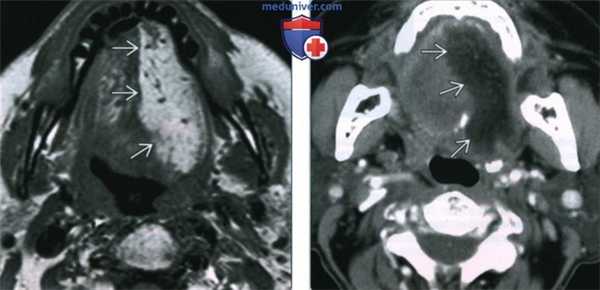

(Слева) МРТ Т2ВИ, аксиальная проекция. Денервация языка в острую стадию. Выраженный отек половины языка с повышением интенсивности сигнала. Обратите внимание на четкую демаркационную линию. Денервация была обусловлена переневральным ростом опухоли вдоль ЧН XII.

(Справа) МРТ Т1ВИ FS с КУ, подострая денервация языка. Накопление контраста в мышцах левой половины языка. Обратите внимание на четкую границу между половинами. Причиной денервации стало метастатическое поражение основания черепа, в том числе подъязычного канала.

• Острая стадия (обычно менее одного месяца):

о Язык отечный, дряблый

о Повышение интенсивности на Т2ВИ, незначительное снижение Т1ВИ

о В острую стадию интенсивность накопления контраста вариабельна

• Подострая стадия (обычно 1-20 месяцев):

о Отек разрешается, жировая атрофия

о Гиперинтенсивный сигнал на Т1ВИ, снижение интенсивности контрастирования

(Слева) На аксиальной МРТ (Т2 ВИ) в острой фазе денервации языка определяется отек и значительное повышение интенсивности сигнала половины языка вследствие отека. Оцените четкое отграничение патологического участка. Причиной денервации стало периневральное распространение опухоли вдоль ЧМН XII.

(Справа) На корональной МРТ (Т1 ВИ С+ FS) определяется признак подострой денервации - неравномерное контрастирование мышц левой половины языка. Обратите внимание, что изменения, обусловленные вторичным поражением основания черепа с вовлечением подъязычного канала, четко отграничены.

• Острая фаза (обычно о Слабость и отек языка

о Гиперинтенсивный Т2 сигнал 1/2 языка, слегка гипоинтенсивный Т1 сигнал

о Вариабельное контрастирование в острой фазе

• Подострая фаза (обычно 1-20 месяцев):

о Разрешение отека, жировая атрофия

о Повышение интенсивности Т1, уменьшение накопления контраста